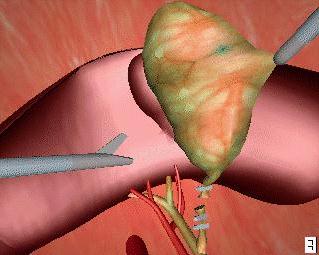

Surgical planning consists of three main parts. These are imaging the patient, creating a satisfactory three-dimensional (3D) model of the imaging data, and planning/rehearsing the operation. The imaging of the patient may be accomplished via various means. The main method is that of computer tomography (CT). CT is the process whereby a stack of cross-sectional views of the patient are taken using magnetic-resonance-imaging or x-ray methods. This kind of imaging is necessary for all types of operative procedure and, as such, does not differ from traditional surgical techniques. This two-dimensional (2D) data must then be converted into a 3D model of the patient (or, more usually, of the area of interest ). The reasons for this transformation are twofold. Firstly, the 2D data, by its very nature, is lacking in information. The patient is, obviously, a 3D object and, as such, occupies a spatial volume. 2D data is just that - two-dimensional; hence it cannot easily provide information pertaining to such issues as volume (of, for instance, a tumour) or, position (with respect to distances perpendicular to the cross-sectional data). Secondly, it is more accurate and intuitive for a surgeon, when planning a procedure, to view the data in the form that it actually exists. The actual transformation into a 3D model is readily accomplishable through volume graphics methods (see Volume Graphics: The road to interactive medical imaging?). These methods produce computer-graphics-based models that possess such features as the ability to rotate the model, view its interior, zoom in, and so on. That is, all the capabilities of current computer-aided-design (CAD) systems. As may be expected, however, the processing requirements of these modelling systems are rather large, as are the costs of the hardware necessary. It should be noted, however, that the speed of said hardware is increasing all the time and the price will decrease too, as the technology involved becomes more commonplace. This means that the process will be more cost-efficient and increasingly routine in the future. The third phase of the planning is the actual development of the plan itself. This involves determining the movements and forces of the robot in a process called 'path planning' - literally planning the paths that the robot will follow. It is here that the 3D patient model comes into play, as it is where all the measurements and paths are taken from. This emphasises the importance of the accuracy of the model, as any errors will be interpreted as absolute fact by the surgeons (and hence the robot) in their determination of the plan. Here, surgeons are reliant upon the engineering behind the system that is being used - thus the need for reliable systems (discussed in the section on safety). |

Fixation is an essential ingredient of a successful robotic operation. Robots act upon pre-programmed paths (as mentioned above), these programs are much more complex (and more difficult to prove for safety aspects) if they must take into account the fact that the patient's position may be different to the inputted data and, in fact, continually changing. For this reason it is imperative that the robot can act in, at least, a semi-ordered environment. Fixation of the patient, that is fixing the patient in position (i.e. on the operating table), is achieved through strapping and clamping of the areas pertinent to the surgery. This is common in traditional surgery, too. For example, the leg of a patient undergoing a knee operation is clamped in position to avoid unintentional movement; similarly, the head is fixed in position during neurosurgery through the application of a head-fixation device known as a 'stereotactic unit'. Fixation of the robot is achieved through analogous methods. Patient held in fixed position for neurosurgery The intra-surgical registration itself is the process of establishing a common reference frame between the pre-surgical data (3D model and associated surgical plan) and the corresponding patient anatomy. Once a common reference is established, pre-surgical data can be safely used to guide robotic movements.There are two primary techniques of achieving this common frame of reference. The first, and most usual, method is to attach fiducials (physically implanted markers) to the underlying patient structures pre- operatively (and necessarily before imaging takes place). These fiducials are then sensed, and compared to the pre-operative data, to precisely align the two data sets. Unfortunately, this 'fiducial- based' registration typically requires an additional surgical operation in itself, in order to attach the markers. Furthermore, these fiducials are invasive and cause added trauma to the patient in sites physically far from the primary field of surgical focus. The alternative to fiducial-based registration is that of 'surface- based' registration. This technique uses surfaces that are intrinsic to the data itself. If surfaces can be extracted from both the pre- and intra-surgical data, then these data sets can be matched to perform registration. The benefit of this method is that it does not require the use of expensive and traumatically invasive markers. The success of surface-registration is highly dependent upon the realism and accuracy of the 3D models gained pre-operatively and upon the sensing accuracy of intra-surgical data acquisition. Geometric surface model validation is complicated since errors can be introduced at several stages of model creation: during imaging, 'segmentation' (seperation of different tissues within a medical image), and surface creation. Prior to the emergence of surface-based techniques for surgery, 3D modelling of medical data has been primarily used as a teaching aid in the study of anatomy (e.g. VOXEL-MAN). These models have very different accuracy requirements to those used for surface-based registration. For instance, the ease with which an object of interest (e.g. a particular organ) can be segmented from surrounding objects is of crucial importance in robotic surgery since any 'blurring' of edges could mean that erroneous incisions are made. Another demand, placed upon the geometric model of the patient, is the ability to cope with 'spatial density' variation within an object. Density variations, like those in real bones and tissue, complicate segmentation by reducing the effectiveness of simple thresholding schemes (methods that interpolate a density from the surrounding data and assign the density value according to certain, pre-determined, thresholds).

Once all of the preparation is complete, it is time to pass control to the robot for the actual implementation of the surgery.

The robots used for automated surgery tend, at the present time, to be adapted industrial robots; for example, the PUMA robot arm. The reasons behind this are predominantly financial ones. Investing in the research and development of a robot for a specific task is highly expensive - costs running into millions of pounds, with no guarantee that a suitable product will be the outcome. Another hurdle is the lack of official safety guidelines and standards. Having brought up the fact that the surgeon is reliant upon the engineering behind the tools that they are using, it is clear that companies would not wish to risk possible legal proceedings should one of their products fail. (These issues will be further discussed in the section on safety). As it stands, industrial robots are adequate for the tasks involved, although it is hoped (and expected) that, in the future, surgery- specific robots will be developed and will become an industry of their own. Once the robotic procedure is initiated, sensors collect real-time data from the operating site and pass this to a display, via which the surgeon observes the operation. The type of sensor that seems to best suit the surgical application is the use of infra-red transmitters on the robot's 'joints', that are detected by cameras in the operating theatre (currently under commercial development by General Electric). From these, the exact position of the robot's appendages can be gauged and relayed back to the surgeon's display. It is an issue as to what control a surgeon should have when overseeing an automated surgery - as they may do more damage than good if they intervene. The most common arrangement is to have a 'stop' switch and perhaps a 'redo' control. Sensing the patient, intra-surgically, is fairly simple when using fiducials (the fiducials are specially made from materials that are easily detectable under the system being used). This is not the case, however, when using the preferred surface techniques. Here a variety of systems are under consideration, including an ultrasound sensor or an x-ray sensor - both mounted on a 'C-arm' so that they can move around the whole area of the patient. |